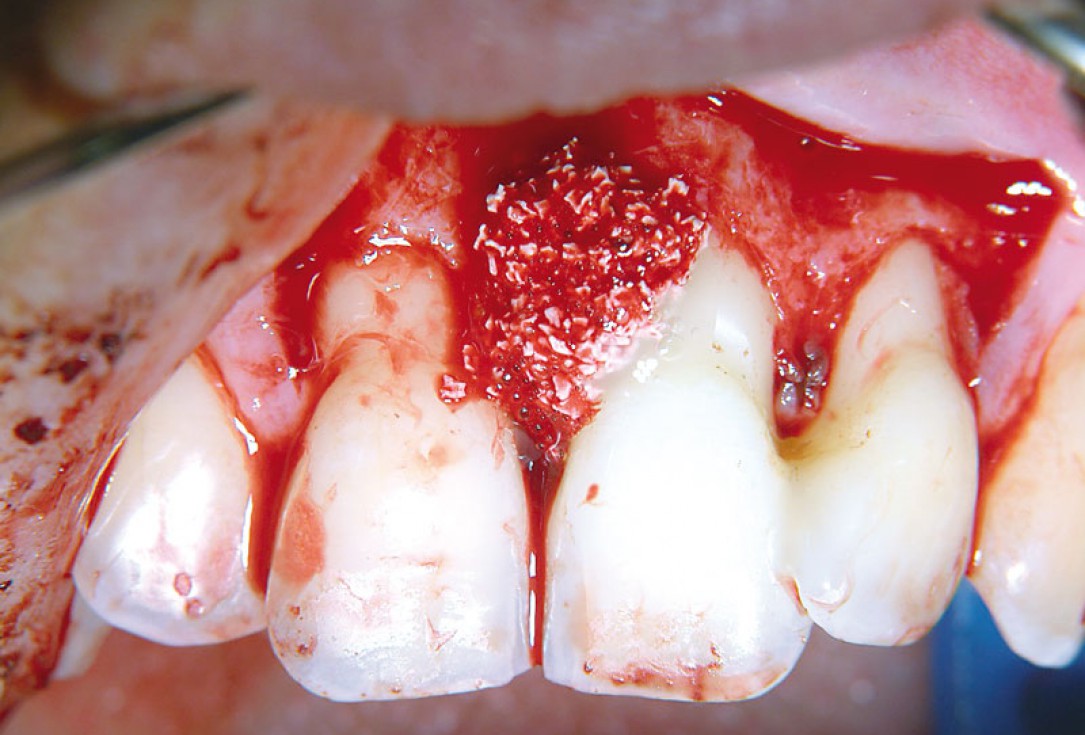

06/11 - Application of small cerabone® granules.Non-contained intrabony defect treated using cerabone®, collprotect® membrane and Straumann® Emdogain® - Dr. T. Schwaar (2)